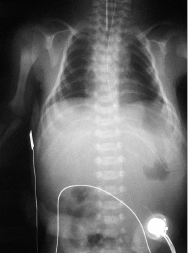

2–3% der Neugeborenen haben angeborene Fehlbildungen, die mit bedeutsamer Behinderung einhergehen oder lebensbedrohend sind, 3–4% der Neugeborenen haben geringfügige Fehlbildungen. Durch die pränatale Ultraschalldiagnostik können zahlreiche angeborene Fehlbildungen bereits vor der Geburt erkannt werden (Abb. 4.3). Bei intrauteriner Diagnose einer angeborenen Fehlbildung sollten die Eltern von Geburtshelfern, Neonatologen und Kinderchirurgen gemeinsam beraten werden und der Geburtsmodus und das postnatale Vorgehen festgelegt werden.